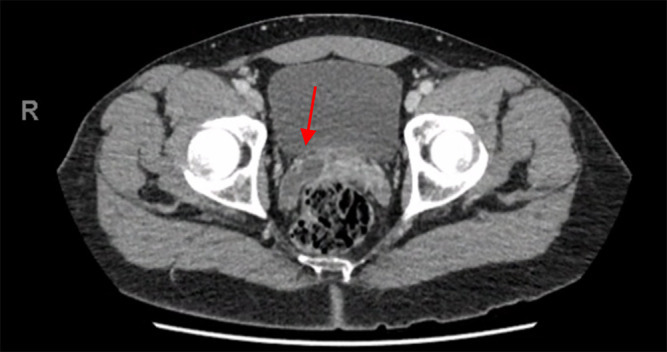

A 44-year-old healthy Caucasian gentleman presented with fevers and right lower quadrant pain. He had mildly elevated inflammatory markers and computed tomography demonstrated cystic enlargement of the right seminal vesicle concerning for seminal vesicle abscess (SVA). SVA is a rare diagnosis and generally requires drainage for adequate source control. The patient was commenced on intravenous antibiotics and underwent uncomplicated transperineal drainage of seminal vesicle abscess under local anaesthetic. Urine culture confirmed infection with Citrobacter koseri and the patient was discharged on the first post-operative day with a 14-day course of oral co-trimoxazole. Six-week follow-up with multiparametric magnetic resonance imaging of the prostate shows no evidence of any prostatic lesions, prostatitis or recurrence of abscess.